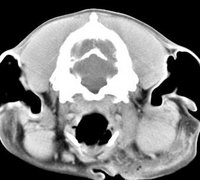

imágenes de TC en el perro | ||||||||||

ejemplo de imágenes de TC en el perro. Nótese la celulitis en la región parotídea izquierda | ||||||||||